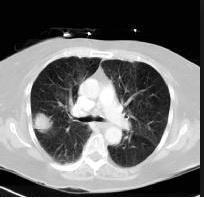

TheproposedsystemismethodicallytestedusingdifferentlungnoduleCTimage.

Fig.1CTscansLungNoduleImages